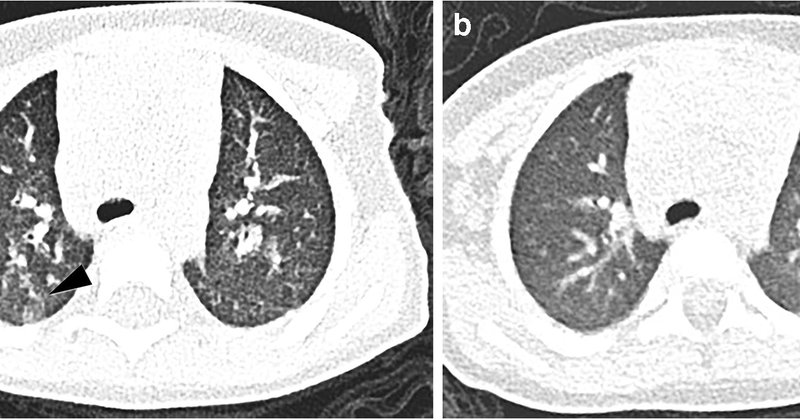

Despite what this article suggests CT should not be used for dx of #Covid_19 in children. No reason to CT asymptomatic children as done here. @SocPedRad @ESPRSociety

https://t.co/MSirKWJb8N

link.springer.com

Pediatric Radiology - Infection with COVID-19 is currently rare in children. To describe chest CT findings in children with COVID-19. We studied children at a large tertiary-care hospital in China,...